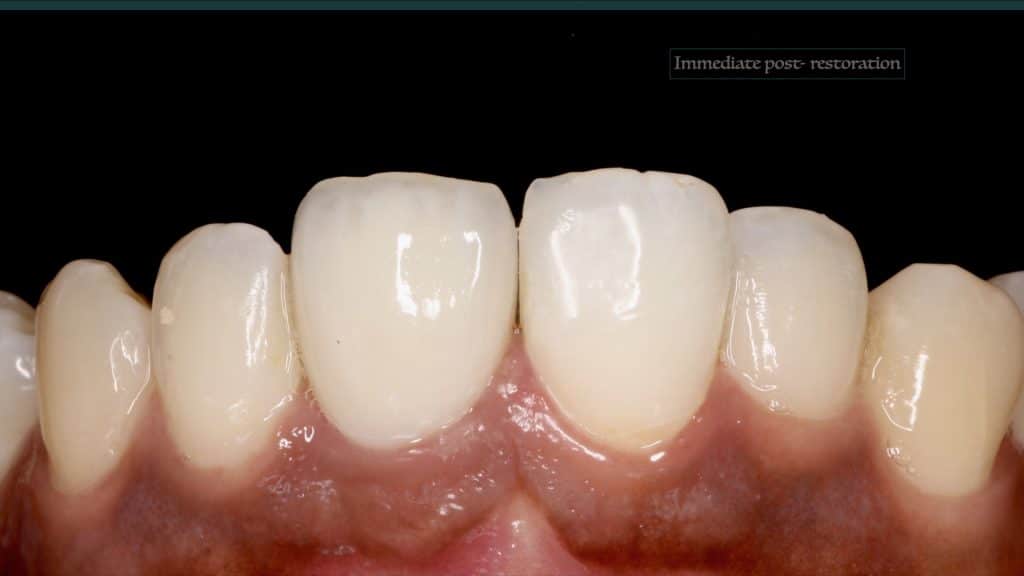

A 27-year female patient with dislodged Resin bonded FPD. She had that FPD for past few years, it had metal wings on palatal surfaces of UR1 and UL2 and a post like metal extension into the root canal of UL1. There was gingival abscess due to fractured root segment most probably due to extended metallic post like structure. Immediate implant placement (IIP) and Immediate restoration (IR) was planned for this patient.

Occlusal check